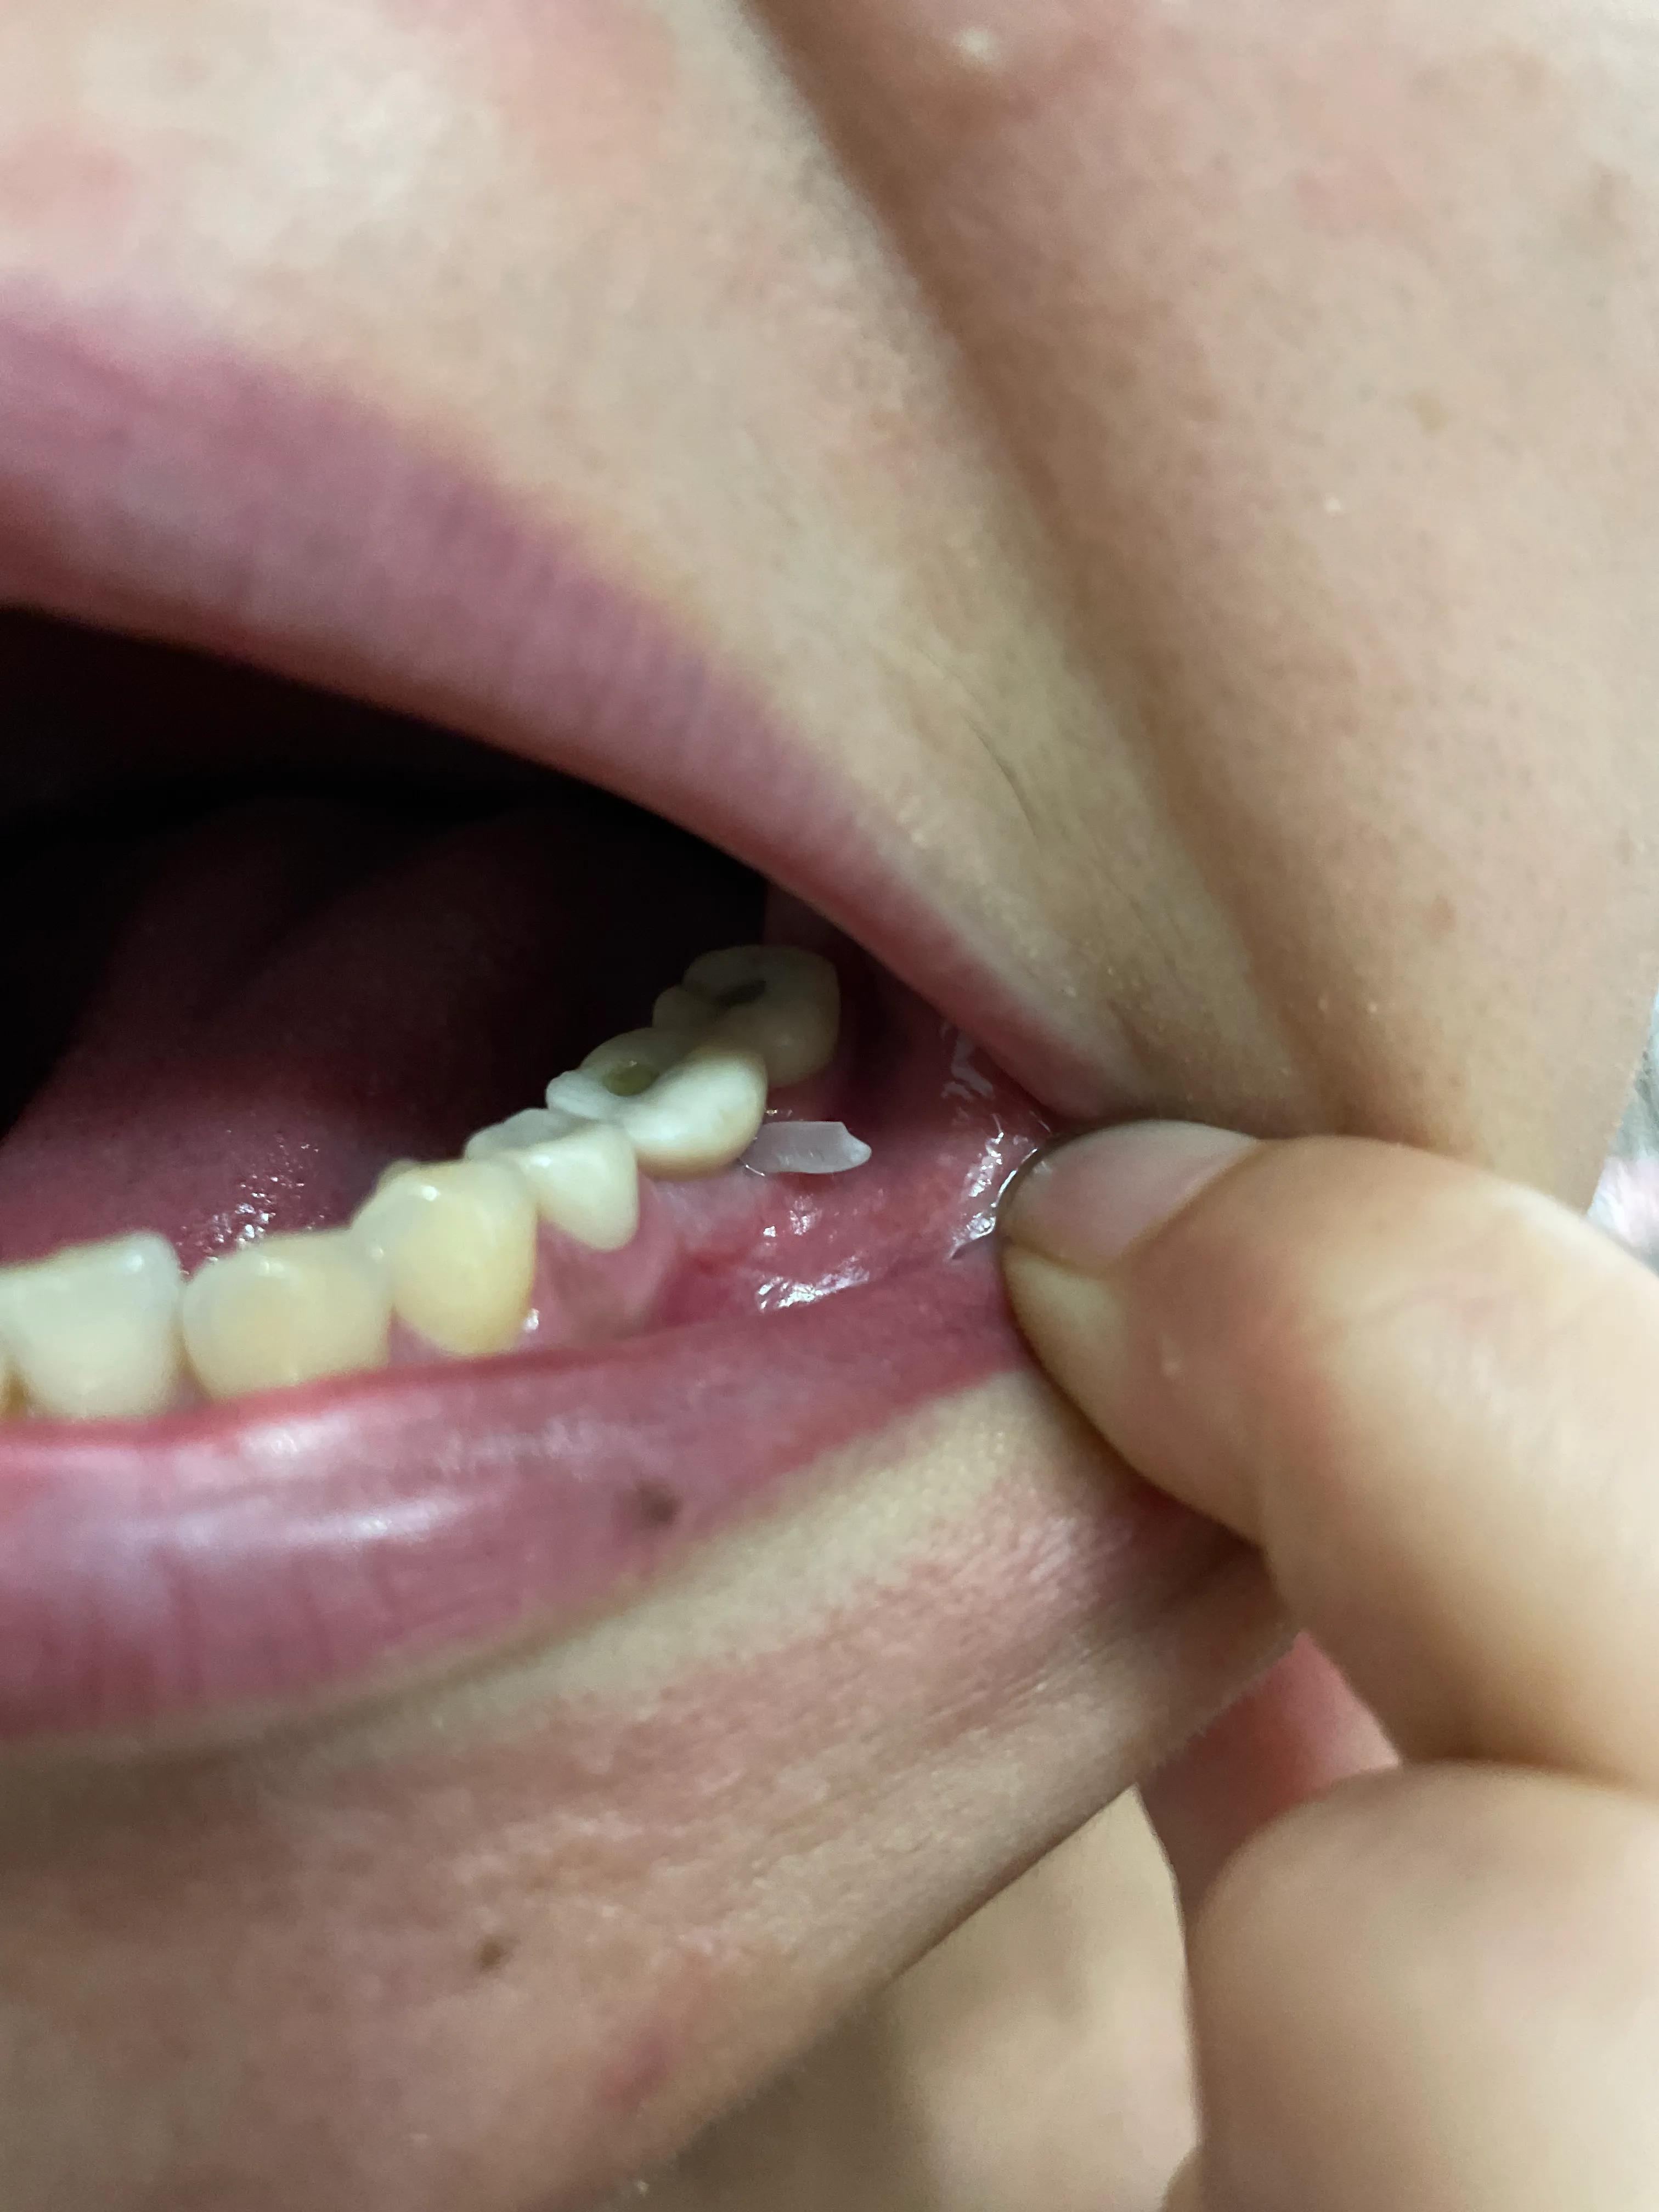

第二副牙帶好 發(fā)現(xiàn)牙齦又缺肉了 更別提貼合牙齒了 而且是一直的疼 一直難受

牙齦是外翻和牙齒分開的 顏色發(fā)白 和其他部位牙齦不是一樣顏色

我不是專業(yè)醫(yī)生 不懂他們所說的正常現(xiàn)象都包括什么 要怎么后期維護(hù) 我現(xiàn)在先不講看不見的難受 疼 先講直觀能看見的 他們哪位醫(yī)生可以做到把大米粒塞到牙齒下面 和將近半厘米的塑料條塞過他們的牙齒 吃過東西就要用沖牙器 不然隔頓就臭了

沒辦法自己又出去拍片子 找原因 看了幾家醫(yī)院 才知道連種植體也種偏了 牙冠也沒有就位………